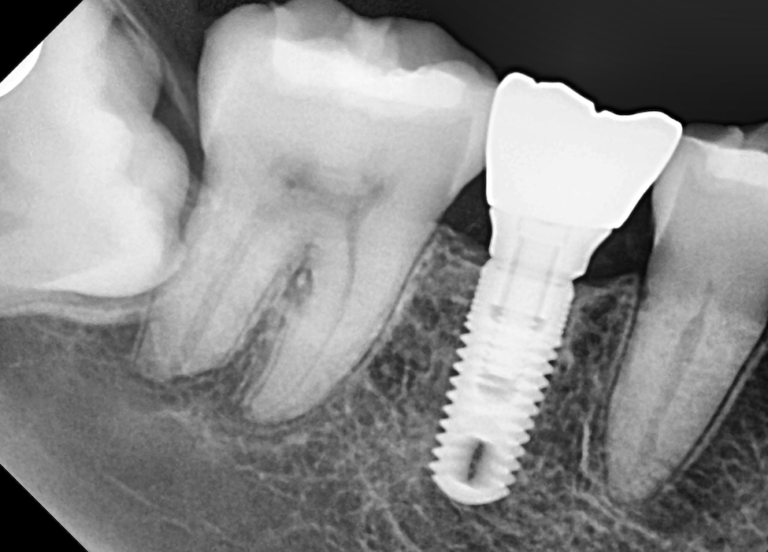

Zirconia Dental Implants Holistic Dental Center New Jersey